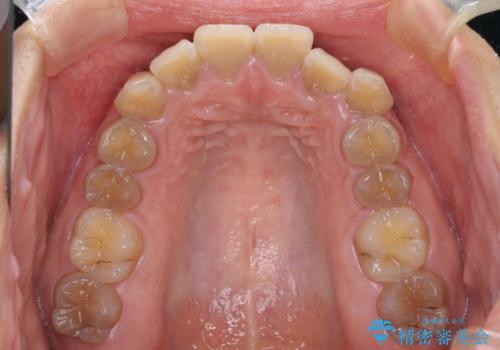

- 口元の突出感を気にして来院された患者様です。

上下前歯が著しく前突している状態であったので、上下左右の第1小臼歯4本を抜歯し、ワイヤー装置にて矯正治療を行うこととしました。

舌の突出癖により、前突になったと考えられたため、舌のトレーニングをしっかりと行うよう指導しました。

4本の歯を抜歯したことで、飛び出していた口元が引っ込み、横顔が大きく改善されました。